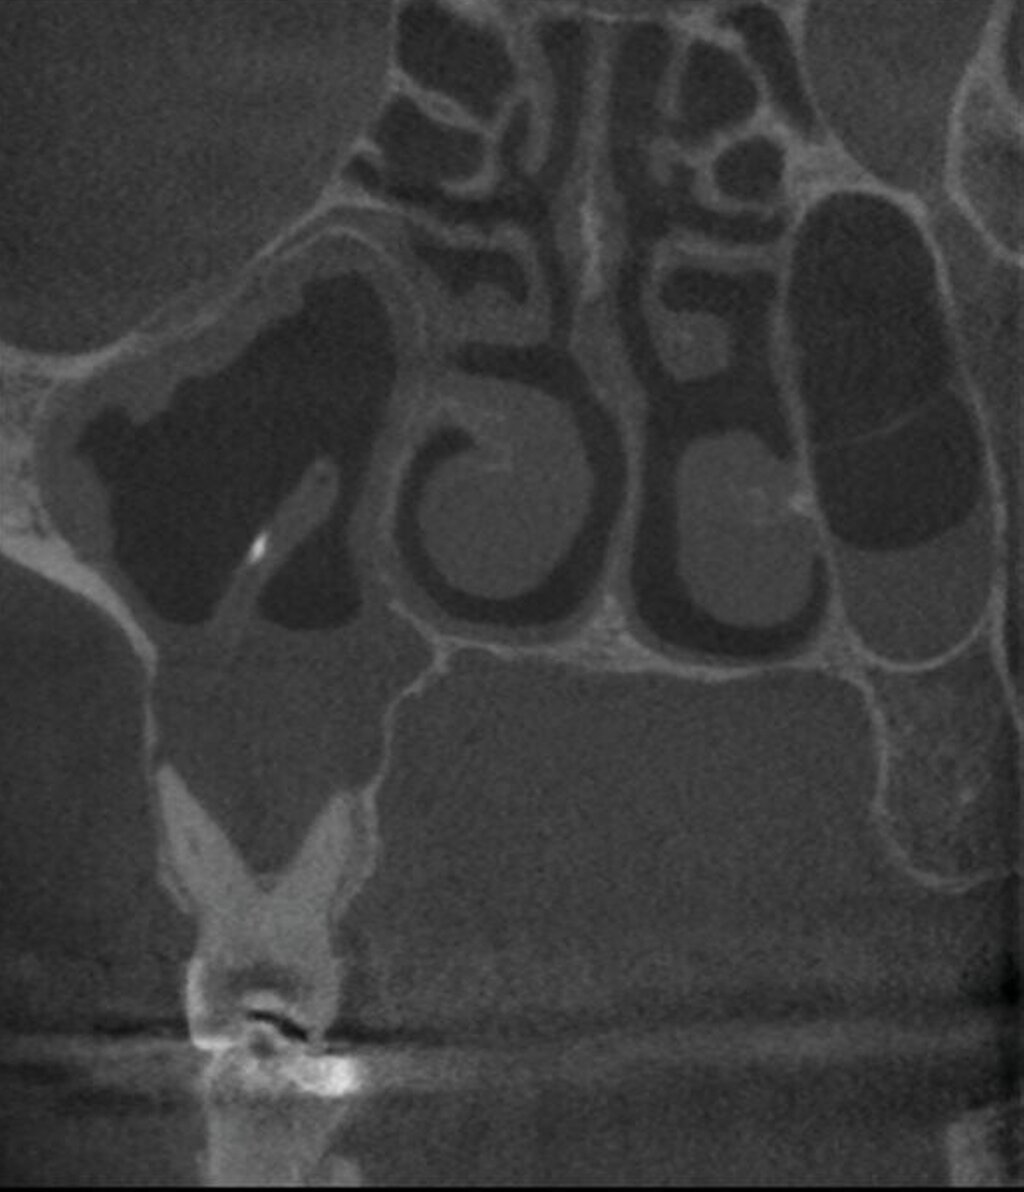

Während DVT-Aufnahmen ausschließlich zur Beurteilung periapikaler Läsionen nur einen begrenzten Mehrwert für die angestrebte operative Therapie liefern, gerät die zweidimensionale Diagnostik zur Beurteilung angrenzender Strukturen wie den Kieferhöhlen an ihre Grenzen. Ausprägung, Lage und Morphologie von odontogenen Kieferhöhlenpathologien lassen sich nur schwer aus Panoramaschichtaufnahmen oder Zahnfilmen ableiten. In circa 30 Prozent der Fälle ist eine Sinusitis maxillaris dentogener Herkunft [Psilas et al., 2021]. Apikale Parodontopathien spielen hierbei eine wesentliche Rolle [Shahbazia et al., 2012; Lechien et al., 2014]. In einer retrospektiven Analyse von Brüllmann et al. [2012] zeigten DVT-Aufnahmen in 74 Prozent der Fälle verdickte basale Schleimhautschwellungen, wenn gleichzeitig entzündliche periapikale Prozesse vorlagen. In zehn Prozent der Fälle wurde der osteomeatale Komplex als „geschlossen“ klassifiziert. Rechtfertigend lassen sich drei Hauptfragestellungen an die DVT-Aufnahme einer fraglichen odontogenen Sinusitis stellen:

Liegen bildmorphologische und lagebedingte Abweichungen im Sinus in Form von Kollateralödemen, Pseudozysten, ins Lumen ragenden radikulären Zysten, basalen beziehungsweise wandständigen Schleimhautschwellungen oder Spiegelbildungen bis hin zu Totalverschattungen vor?

Ist das Ostium naturale nachvollziehbar und damit die Funktionsweise der Kieferhöhle intakt?

(soweit das Volumen des DVT-Geräts dies zulässt): Liegt eine Ausbreitung der Sinusitis maxillaris in die benachbarten Nasennebenhöhlen (Pansinusitis) vor?

Diese Informationen sind wichtig, um den Umfang des chirurgischen Eingriffs entsprechend planen und gegebenenfalls differenzialtherapeutische Erwägungen anstellen zu können (Abbildung 5). Bei Vorliegen einer Pansinusitis ist zusätzlich eine rhinogene Ursache in jedem Fall abzuklären.